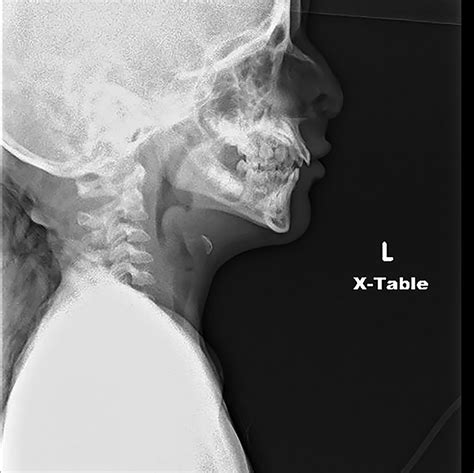

Radiological Identification: The Thumbprint Sign

The Thumbprint Sign Epiglottitis is observed on a lateral soft tissue neck X-ray. Under normal conditions, the epiglottis appears as a thin, wispy shadow. In cases of acute epiglottitis, the inflamed tissue projects posteriorly and superiorly, creating a rounded, dense, soft-tissue opacity that resembles the distal phalanx of a human thumb. Hence, it is commonly called the "thumbprint sign."

The reliance on the Thumbprint Sign Epiglottitis must be balanced with the clinical stability of the patient. If a patient is stable, a lateral neck radiograph can confirm the diagnosis. However, if the patient is in severe respiratory distress or is showing signs of impending airway failure, the diagnosis should be made clinically. In these scenarios, moving the patient to the radiology department is dangerous.